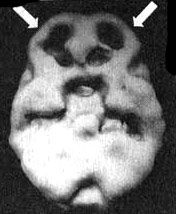

Мозг Боба - СДВ

При концентрации - выраженный спад активности префронтальной коры.

Результаты SPECT только подтвердили мои догадки, возникшие после девяти месяцев регулярных консультаций. Более того, я разозлился на себя, что не назначил это исследование раньше. В поясной зоне у Бетси наблюдалась чрезвычайно высокая активность, из-за чего ей и не удавалось перефокусировать внимание. Именно из-за этого она постоянно замыкалась на определенных мыслях и идеях. Ее мозг заставлял ее все время возвращаться к одним и тем же переживаниям. У Боба картина была другой. В состоянии покоя мозг выглядел совершенно нормально. Но когда его просили выполнить задание на концентрацию внимания, активность во фронтальных долях, которая в норме должна была бы возрасти, у него почти полностью прекращалась. На практике это означало, что чем больше внимания он пытался уделить Бетси, тем хуже у него это получалось. Порой он стремился к конфликту, чтобы таким образом стимулировать свой мозг. Симптомы Боба и картина, выявленная в результате исследования, подтверждали, что он страдает выраженным синдромом дефицита внимания - как и его дети. Этот синдром часто передается по наследству.